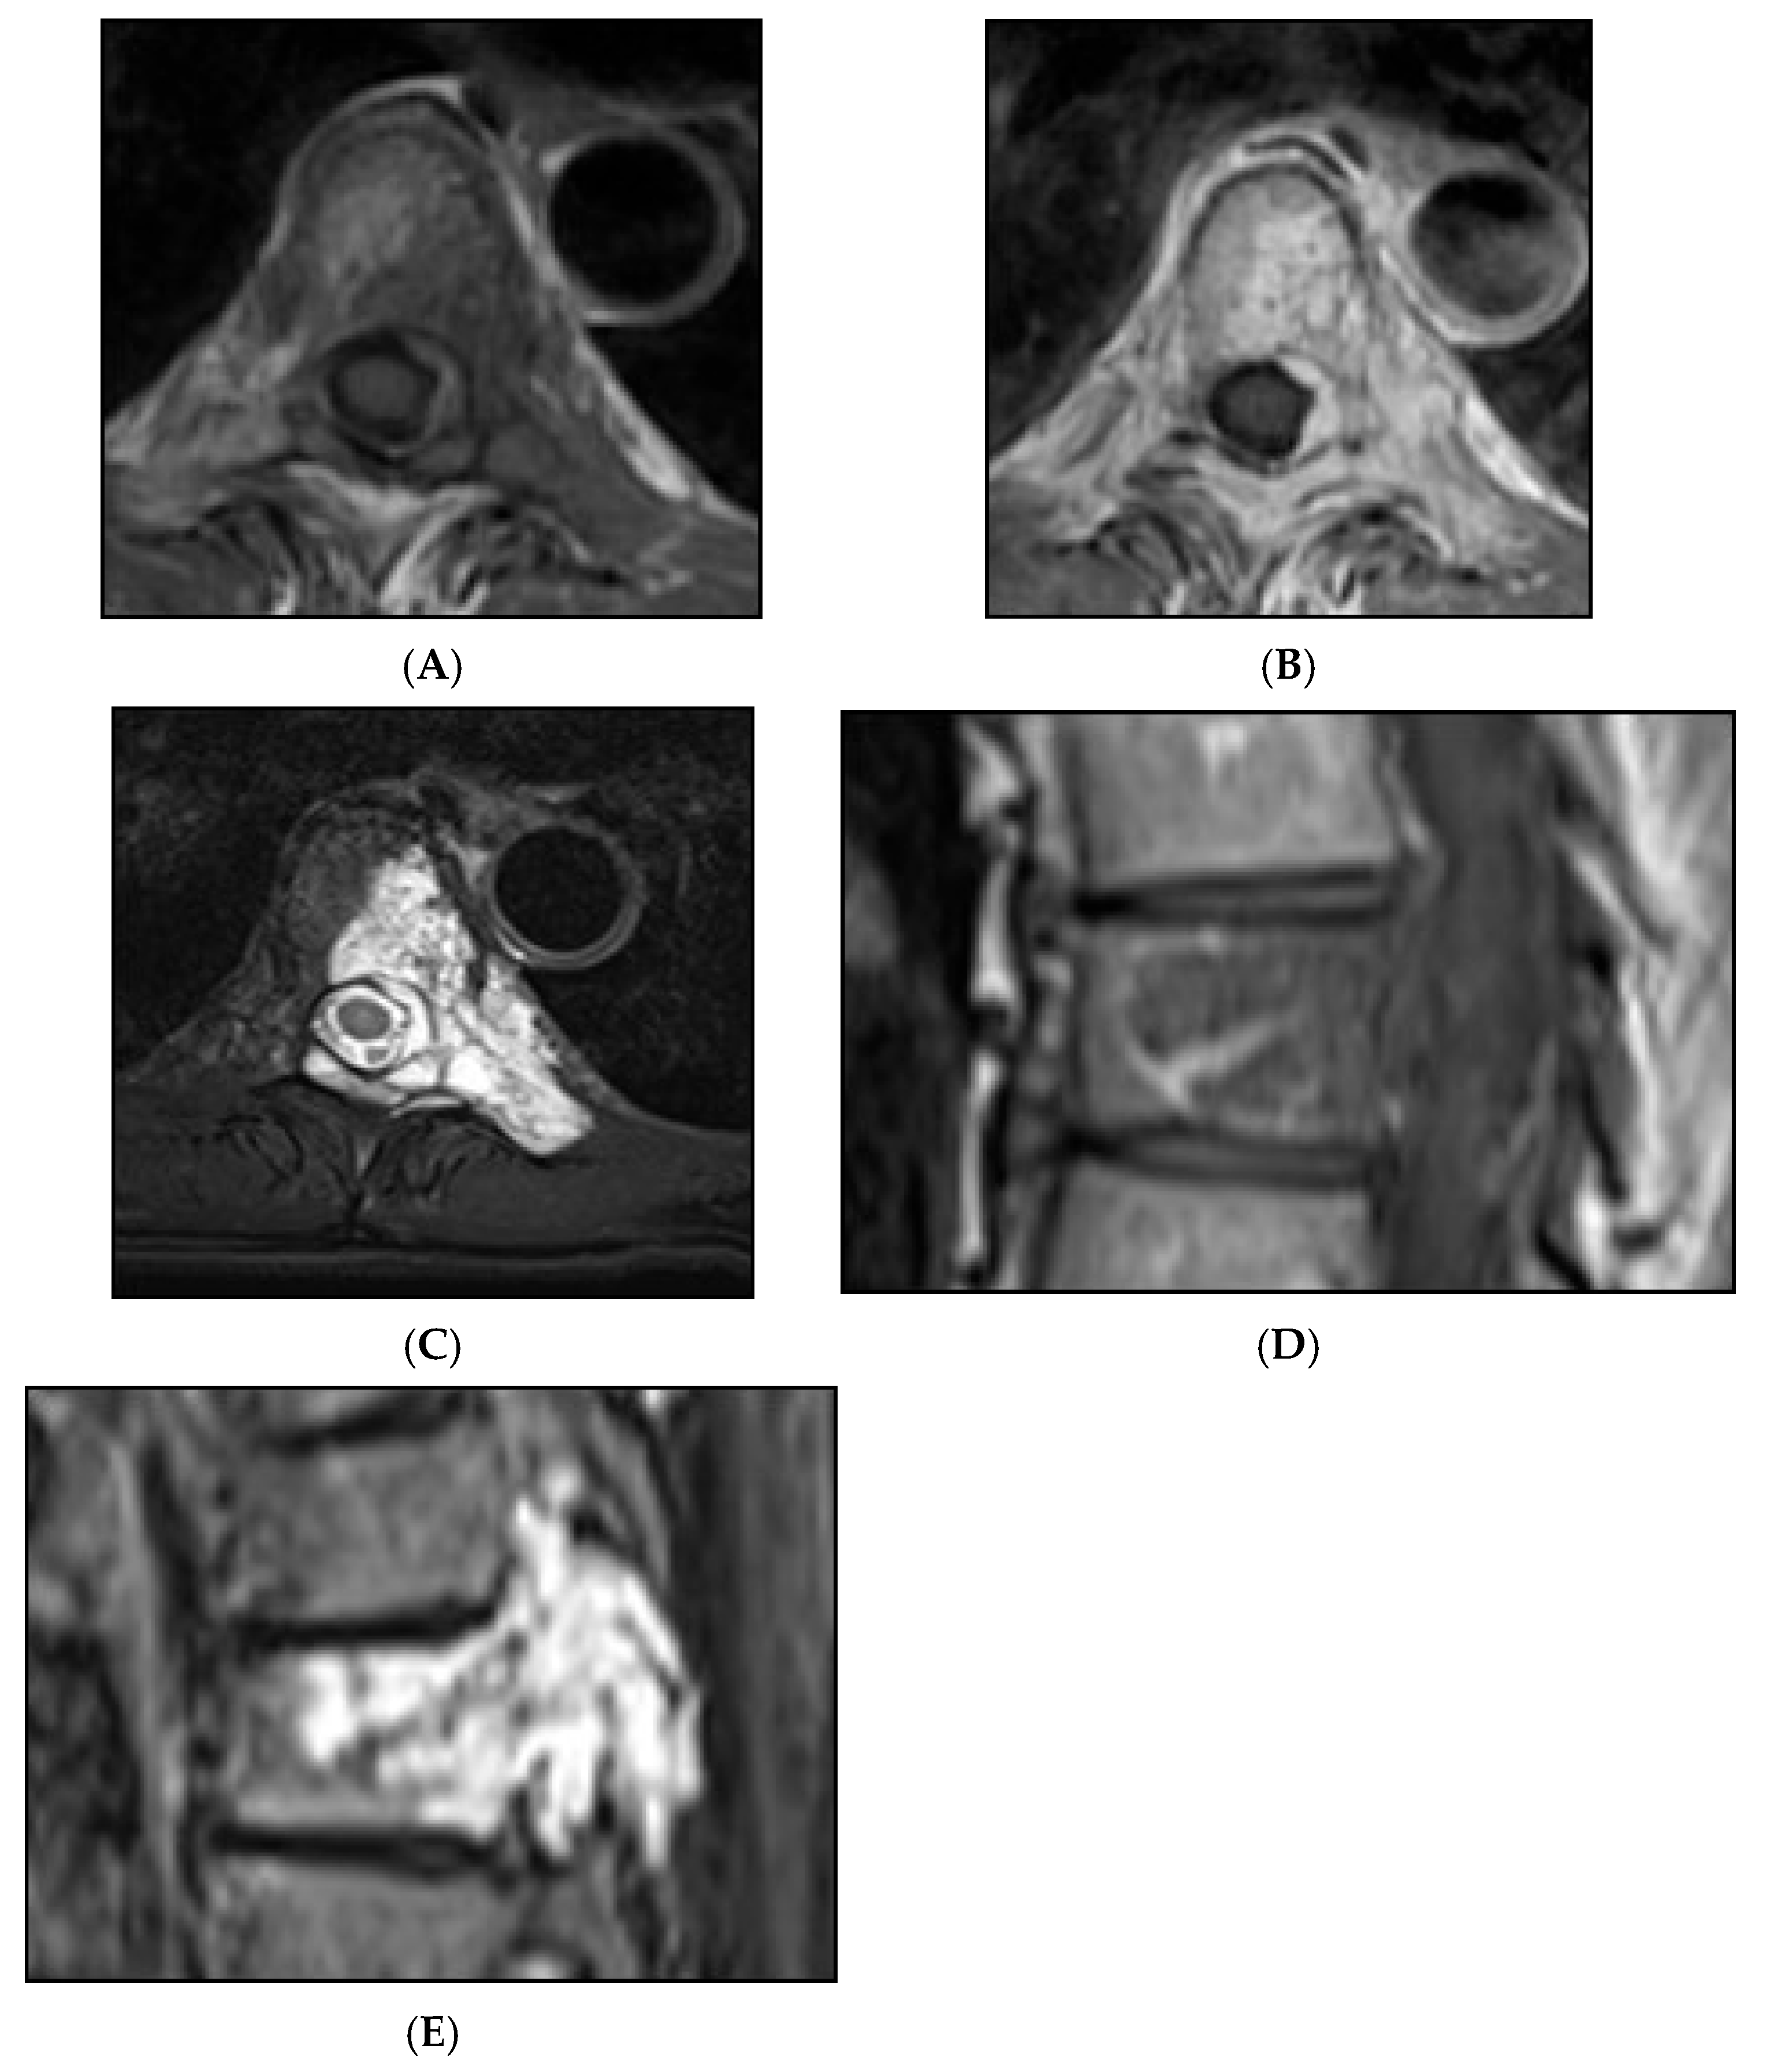

Figure 12.

Aggressive spine haemangioma with involvement of the vertebral body and posterior elements with cortical expansion. (A) Axial T1W MRI. (B) Axial T1W post-contrast MRI. (C) Axial STIR MRI. (D) Sagittal T1W MRI. (E) Sagittal STIR MRI.